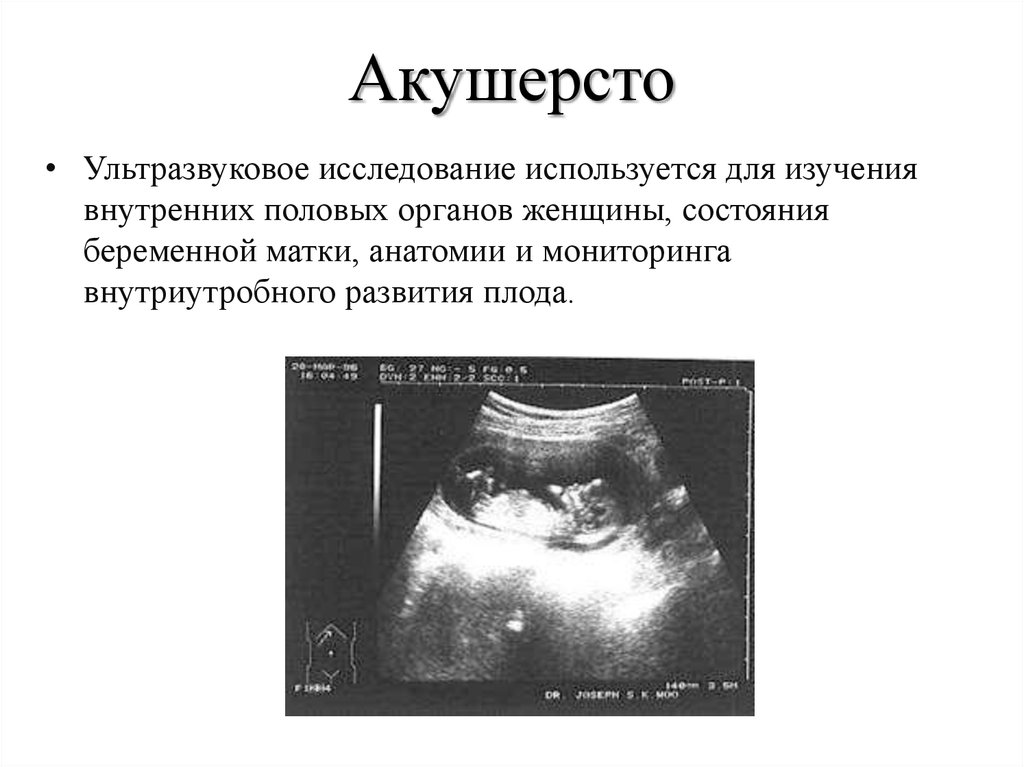

Раздел: Фотогалерея мыслей